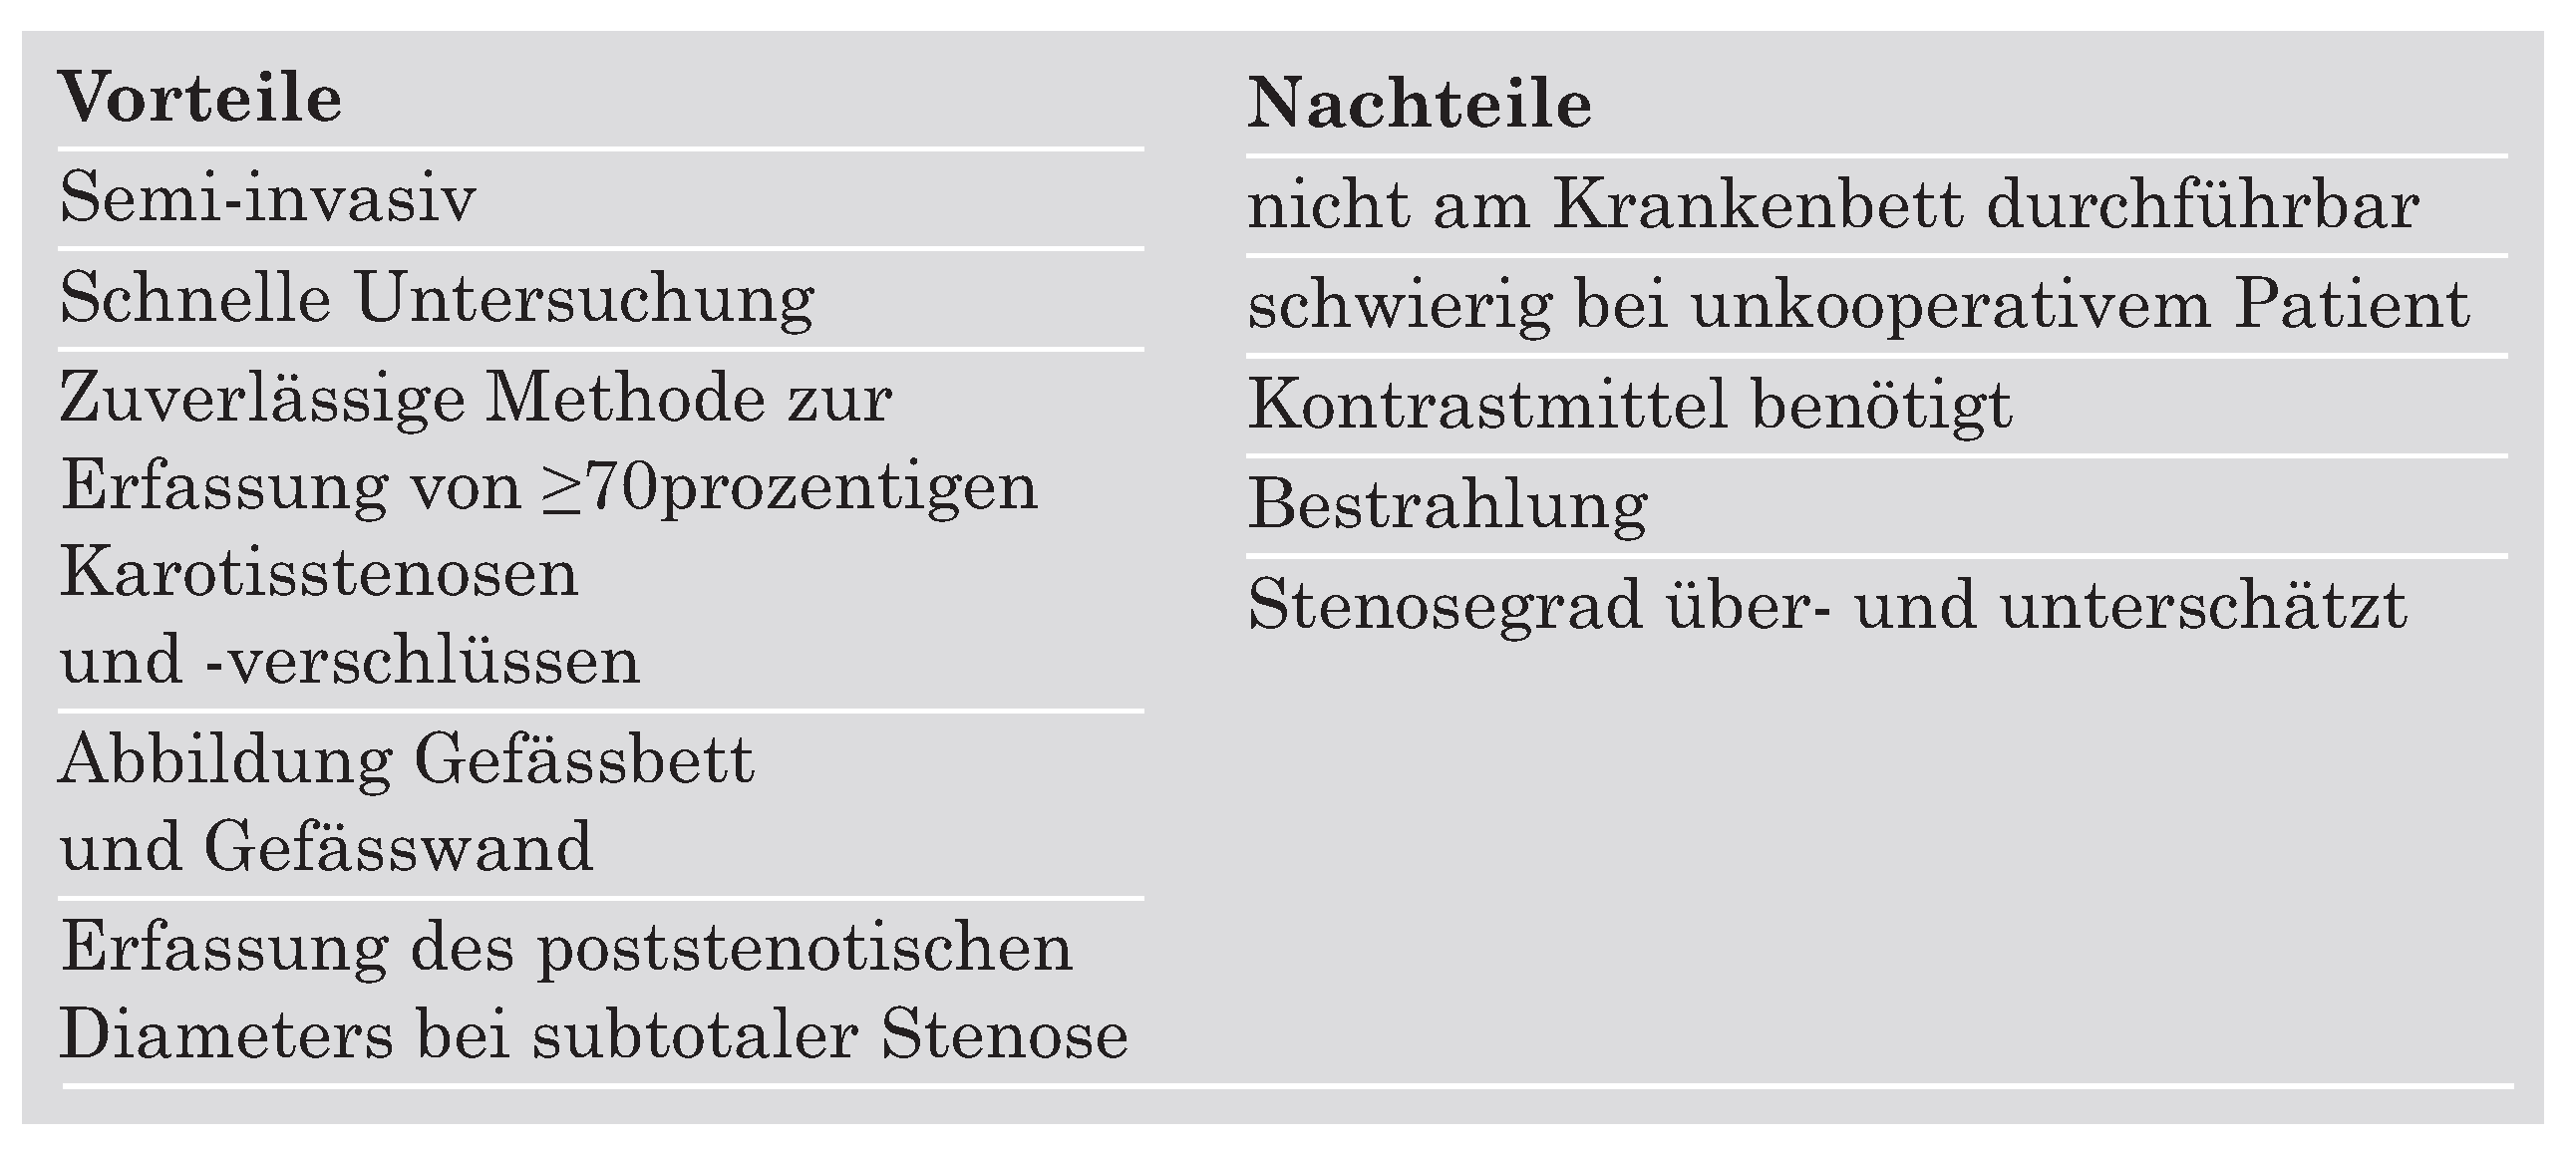

Ultrasonographische Verfahren